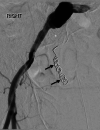

Arterioureteral fistula (AUF) is a direct communication between the ureter and an artery and is a rare cause of catastrophic, life-threatening haematuria. Fistulation may occur between the ureter and the abdominal aorta, common iliac, external and internal iliac, and inferior mesenteric arteries, and is typically observed in patients with a prior history of pelvic radiotherapy, oncological pelvic surgeries, aortoiliac vascular procedures, and pelvic exenteration. There is also an increased frequency of cases amongst patients who have undergone urological diversion surgeries and in those with chronic indwelling ureteric stents requiring repeated exchange. As AUF is so rarely encountered in clinical practice, the urologist may fail to appreciate its presence until late in the patient's presentation; such diagnostic delay is associated with high mortality and thus rapid clinical suspicion and investigative action are necessary. There are sporadic cases of this rare entity mentioned in literature. In this report, we present two cases as well as a review of the literature. A 73-year-old female presented with repeated episodic haematuria for a week in whom the cause of symptoms remained persistently elusive despite repeated imaging and operative approaches. An eventual diagnosis of a secondary right internal iliac-ureteral fistula was ascertained on a subsequent digital subtraction angiography of the renal tract. The fistula was embolised using an endovascular approach. The patient remained stable post emobilisation and was successfully discharged shortly after the procedure. In the second case, a 51-year-old female, presented with hematuria from her ileal conduit for a few days. Initially, the cause of symptoms was thought to be due to ureteric stents. During a change in her stents, brisk bleeding led to further investigation including an iliac angiogram confirming bleeding from the left common iliac artery. She had a covered common iliac artery stent, which successfully controlled her bleeding This report emphasizes the diagnostic difficulty of AUF, outlines the management principles of this rare disease, and aims to increase awareness of this rare yet potentially lethal phenomenon among practitioners of urology and interventional radiology.